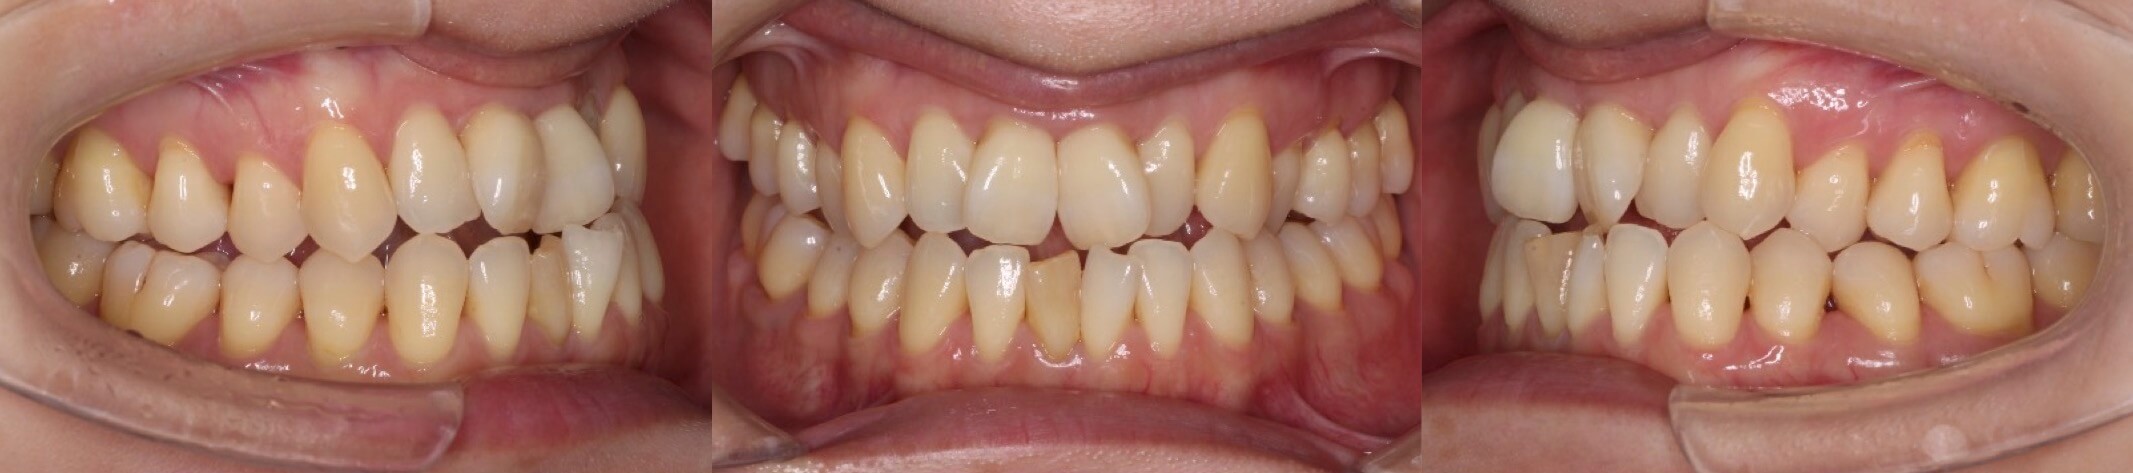

42歳女性・重度叢生・マウスピース装置

ミドルエイジの矯正治療では、できる限り抜歯を併用しないのですが、このように重度のがたつきがある場合は、抜歯を併用します。

<症例概要>

主訴:がたつき

年齢・性別:40代女性

住まい:千葉県佐倉市

症状:叢生・下顎右辺・右II級

抜歯:上左右4番・左下4番(計3本)

治療方針:抜歯空隙閉鎖

治療装置:マウスピース型矯正装置(アライナー装置)

治療期間:2年0か月

アライナー枚数:34+27-14ステージ

リテーナー:上フィックスタイプ+プレートタイプ

治療費用:990,000(税込)

代表的副作用:痛み・治療後の後戻り・歯根吸収・歯髄壊死・歯肉退縮

▶︎その他の副作用

【治療シミュレーション】

上の抜歯空隙に、ゆっくりと確実に犬歯を移動させます。